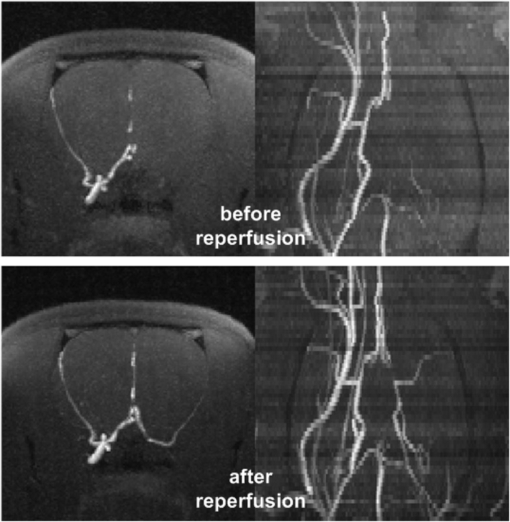

Angiographic images before and after arterial reperfusion in one rat are shown in figure 2. The lack and also the restoration of arterial perfusion in the left MCA (right side in the images) is notable. The multinuclear 23Na/1H MRI data set for the same rat is presented in figure 3. The quantitative results for the tMCAO experiment are summarized in table 1.

Figure 2. Axial (first row) and coronal (second row) maximum intensity maps of arterial blood flow weighted 1H MR images during (first row) and after transient 90 min middle cerebral artery occlusion (second row). Excellent arterial reperfusion was established directly after filament removal.